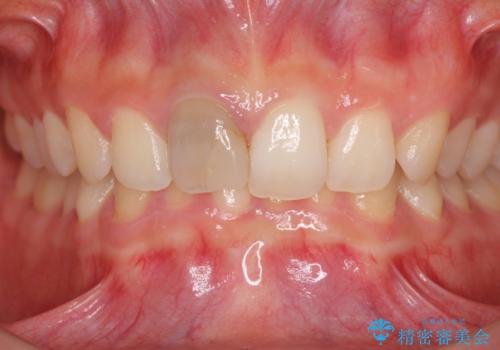

ぶつけて変色した前歯 オーダーメイドタイプのオールセラミッククラウン

- 中学生の時にぶつけて神経を取り除いた前歯の変色が気になるとのことで来院された患者様です。

レントゲン写真より、歯根の炎症が認められなかったため、ファイバーコアによる土台築製後、オーダーメイドタイプのオールセラミッククラウンにて補綴することとしました。